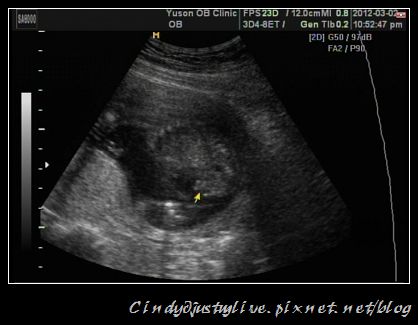

其實我在一剛開始照超音波的時候,我就一直覺得那個凸凸的就是代表是男生了,所以也一直盯著看,醫生一坐下也在笑說要放榜了。因為有之前的夢,再加 上我也一直認為就是男生,果然醫生看了就說:「嗯!要準備藍色的衣服喔!」(因為之前法令規定不能告知性別,所以醫生就要用暗示法來告知。)

有小雞雞啊!